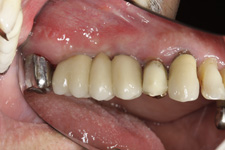

V případě chybění většího počtu zubů v postranních úsecích čelistí je možné ošetření pomocí implantátů, které nahradí ošetření pomocí snímacích náhrad kotvených na zbývajících zubech nebo patře.

Podmínkou je opět dostatečné množství kosti.

Protetické řešení může být pomocí můstku, který je kotvený na implantátech nebo pomocí jednotlivých korunek na implantátech.

Zdravé zuby zůstanou zachovány a přitom náhrady jsou pevné, jako na vlastních zubech